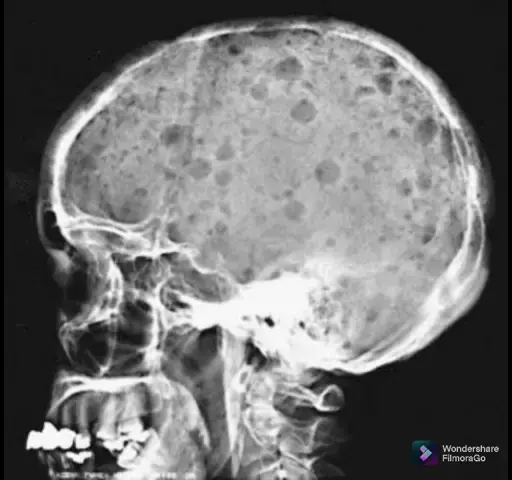

Mieloma Múltiplo... #KwaiConquistar50k #kwaioriginal #Halloween50k #sejacriador